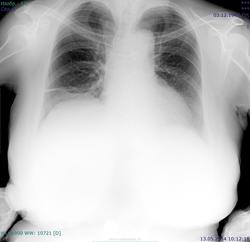

Пациентка 1945 г.р. Флг для ВТЭК, жалоб особых нет, температура нормальная, дыхание свободное. Архив от 2010 - без особенностей. В начале апреля 2014 г АКШ, согласно выписке R перед операцией - без особенностей, после операции - отмечалось высокое стояние пр купола диафрагмы. Самих снимков нет. Дисковидный ателектаз в S9 справа, тень с четкой верхней границей (в медиальных её отделах) над диафрагмой на прямом - признаки гиповентиляции? Или тень - плевральные наложения? Требуется ли контроль\дообследование?

Состояние после стернотомии.Линейная тяжистость в нижней доле справа( фиброз). Релаксация правого купола диафрагмы.( Дообследование не требуется).

Не нахожу ателектаза.Фиброз.

Нет, тут нечего дообследовать. Высокое стояние правого купола отмечалось и после операции

Я считаю, плевродиафрагмальной швартой ( гляньте на боковой. Или стрелку рисовать?)

ХЗ, скиалогия какая-то, может организовавшаяся жидкость в междолевой щели.

Это вполне может оказаться жидкость с заходом в нижние отделы главной м/долевой щели, уже осумкованная,и в малом количестве. Базальные сегменты поджаты( дисков. ателектаз) -горизонт. тень. Со временем все рассосется.Но купол останется высоким, если не "раздышится".При R-контроле все увидите.